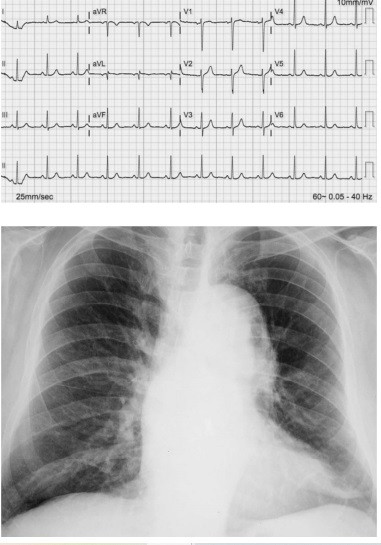

Uma paciente de 61 anos de idade compareceu à emergência com queixa de dor torácica. Havia três horas iniciou um quadro de precordialgia muito intensa do tipo lancinante e com irradiação para a região torácica dorsal. Ela tratava hipertensão arterial sistêmica com hidroclorotiazida 25 mg ao dia, irregularmente, havia 14 anos. Ao exame físico encontrava-se, acianótica, sudorética, com pressão arterial de 176 mmHg × 114 mmHg, saturação de oxigênio em ar ambiente de 93%, pulsos reduzidos em membros inferiores, ritmo cardíaco regular em dois tempos sem sopros, com ausculta pulmonar normal. O restante do exame físico foi normal. A dosagem das enzimas cardíacas (CK-MB massa e troponina) e os demais exames laboratoriais de rotina foram normais. Realizou um eletrocardiograma e uma radiografia de tórax que podem ser vistas a seguir.

Nesse caso clínico, a conduta correta a ser tomada com relação a essa paciente é